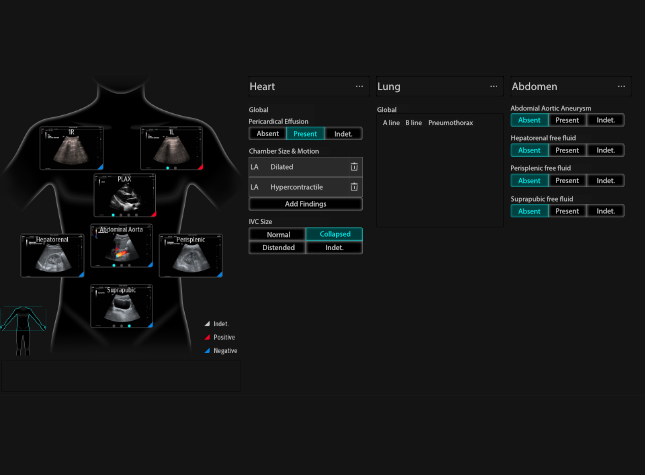

X-Pilot: Clinical Application-Oriented Workflow

Based on the professional society guidelines for point of care ultrasound, the X-Pilot suite integrates historical diagnostic images and multi-organ data into a concise and precise view of the patient status to support rapid clinical decisions at the bedside.